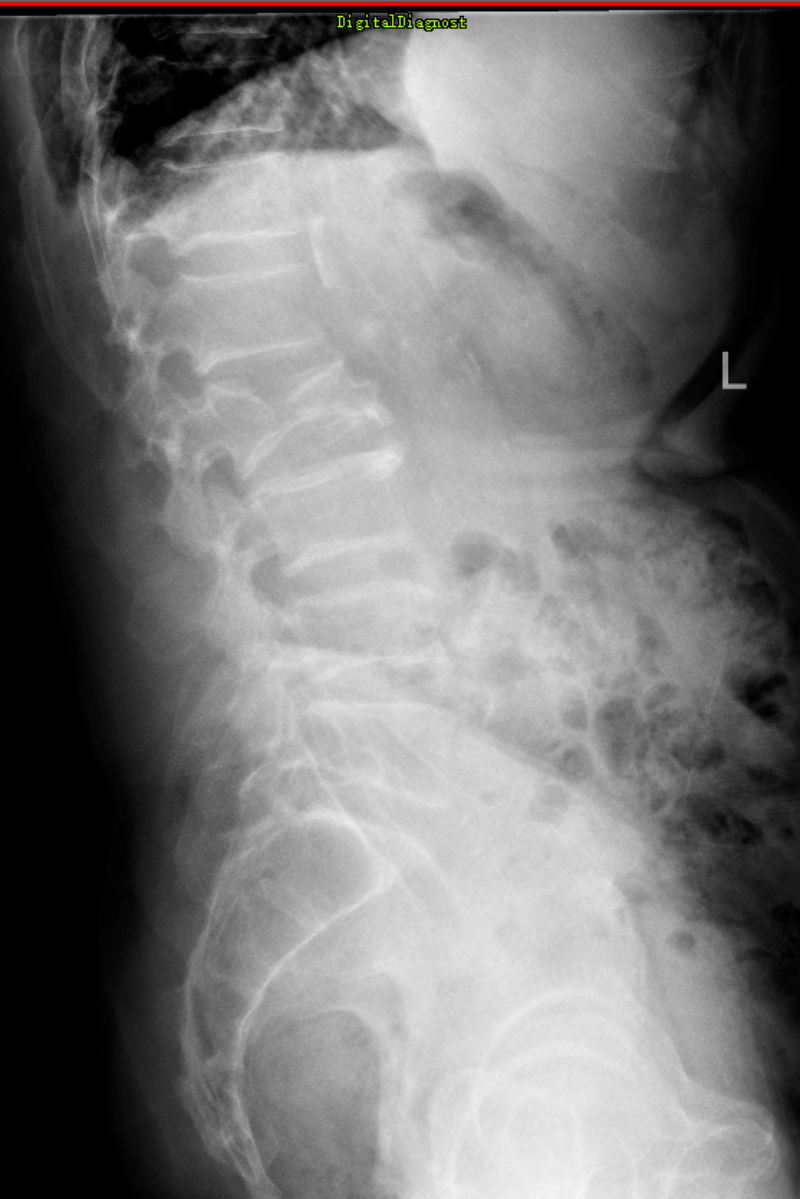

60歲的廖叔,因不小心跌倒,致腰背部疼痛、活動受限,在家自己吃止痛藥、休息后仍感腰背部疼痛難忍,萬般無奈之下,到我院就診,門診行腰椎CT檢查明確為腰2椎體壓縮性骨折,后便安排住進了脊柱外科。患者平時有高血壓病、心律不齊,長期服藥質量,對于手術抱有疑慮,感覺手術風險相當大,住院后姚仕奮及其團隊對廖叔完善相關檢查,評估其身體狀況還可以,并沒有手術禁忌癥,姚仕奮與廖叔及其家人進行了詳細的溝通,告訴他手術創傷并不大,做完手術在支具保護下第二天即可下地活動,廖叔及其家里人了解病情后,決定手術治療。

姚仕奮及其團隊與麻醉科主任孫岸靈團隊為廖叔完善術前準備,在麻醉團隊的保駕護航下,于2023年10月20日為廖叔完成了腰2椎體壓縮性骨折后路切開釘棒系統復位內固定術+植骨術,1小時內便完成了手術,術后護士長龍婷帶領團隊為廖叔制定了詳盡的護理方案,指導廖叔康復鍛煉。術后第2天,廖叔在脊柱外科醫護人員的指導下,已可自行下地活動,恢復十分良好,于11月3日順利出院。

這是脊柱外科開科以來的第一臺手術,也是脊柱外科的常規手術之一。每年都有大量外傷患者胸腰椎骨折需行手術治療,脊柱外科的開科,專科化的技術,能更精準、高效的為此類患者進行手術診治。